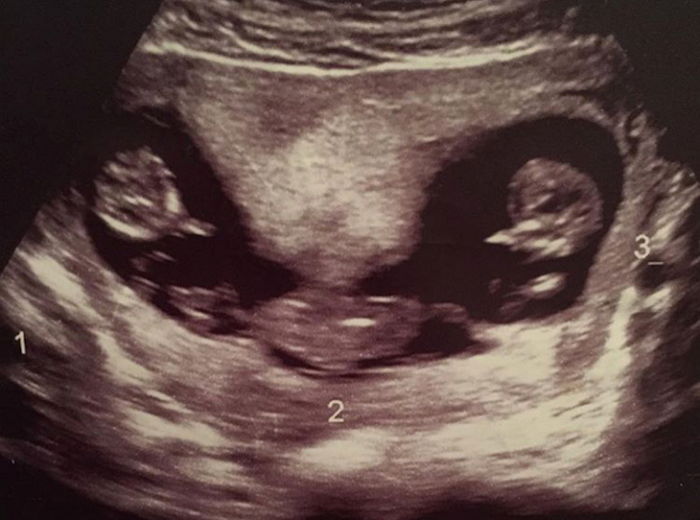

실제 초음파를 통해 아기집에서 편안히 누워있는 세쌍둥이를 만나게 되었고, 이들은 세상에 나갈 날만 손꼽아 기다리며 쑥쑥 자라고 있었다.